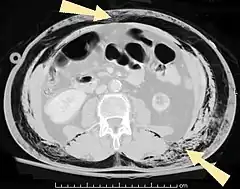

An abdominal CT scan of a patient with subcutaneous emphysema (arrows)

Subcutaneous air (arrows) can be seen as black areas on this pelvic CT scan.